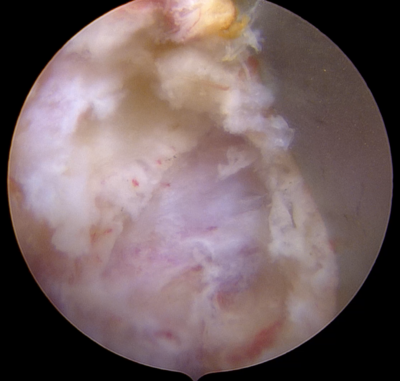

国内で施行されている脊椎内視鏡手術にはいくつかの方法があります。UBEはUnilateral Biportal Endscopic spine surgeryの略称で、BESSはBiportal Endoscopic Spine Surgeryの略称です。2つの呼び名がありますが、どちらも同じ手術方法です。カメラを挿入するための穴、手術器械を挿入するための穴、それぞれ5mm程度の小さな傷をあけ手術を行います。2つの穴から操作をしますので、手術の操作性が良好で、還流液がスムーズに流れ、良好な視野が得られることにより安全に手術が可能です。

いままでの脊椎内視鏡にはMEDと呼ばれているものがあり、約16mm径の筒を挿入して、その中で手術操作を行うものでした。体型の大きな方や脊柱のより深いところの治療を行う場合には操作性が悪いことがありました。一方、UBE/BESSは筒を挿入する必要はなく、直接カメラや手術機器を傷の中に入れて治療を行いますので、いままで届かなかった部位まで手術機器が届きます。また、操作性の自由度が非常に高いため、いままでの脊椎内視鏡手術で不可能であった治療も可能にしております。さらに、手術部位に生理食塩水を還流させながら行う手法で、細いカメラを直接病変部付近まで近づけることが可能なので、非常に良好な視野を得ながら安全に手術を行うことが可能です。

FESSの特徴

いままでの脊椎内視鏡にはMEDと呼ばれているものがあり、約16mm径の筒を挿入して、その中で手術操作を行うものでした。体型の大きな方や脊柱のより深いところの治療を行う場合には操作性が悪いことがありました。一方、FESSは8-10mm程度の傷で専用の器械を直接病変部位に挿入し、ヘルニアを切除したり神経組織の圧迫を取り除くことが可能です。手術によって損傷される背中の筋肉は最小限であり、術後の疼痛をできるだけ少なくすることが可能です。そのため、術後早期にリハビリが可能となり、仕事への早期復帰も実現可能です。